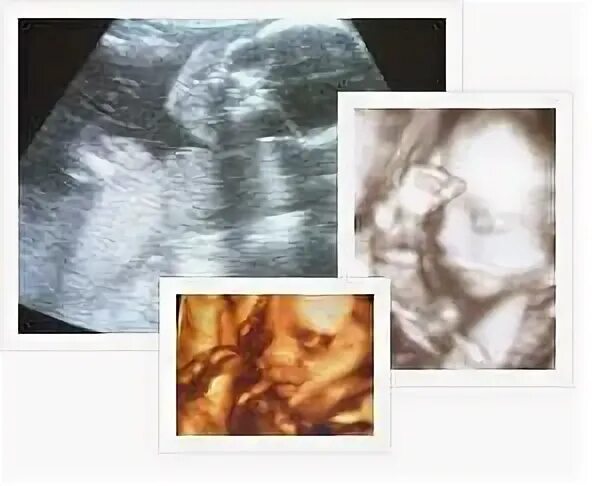

Узи 22 недели